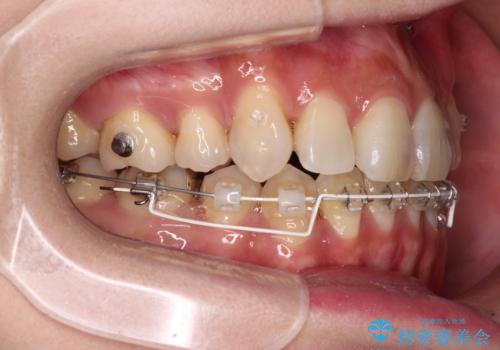

- ハーフリンガル

目立たない装置を希望されたので、上顎が裏側装置のハーフリンガルを選択し、上下左右の小臼歯(計4歯)を抜歯して矯正治療を行うこととしました。

補助装置を併用することで、八重歯を速やかに改善し、治療期間の短縮を図ることとしました。

ハーフリンガルでの矯正治療は、表側矯正よりも期間がかかることが多く、抜歯矯正では3年以上かかることも珍しくありません。

デコボコが強い一方で出っ歯ではなかったため、抜歯したスペースを容易に閉じることができ、短期間での治療となりました。